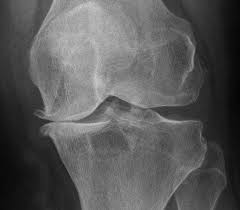

May 05, 2021 · knee osteoarthritis is the most common form of osteoarthritis. Osteoarthritis is a condition that causes joints to become painful and stiff. This condition is a common cause of back pain in older adults and is often the result of internal damage or degeneration of the facet joints. Low level laser therapy (lllt) was introduced as an alternative noninvasive treatment for ra and oa about 10 years ago, but its effectiveness is still controversial. Montag, 27.01.2020, 21:00 uhr die wichtigsten fakten im überblick: Managing the disease helps to preserve range of motion, mobility, and joint function. Cependant, si le traitement médicamenteux peut soulager les douleurs liées à l'arthrose, il ne peut pas stopper son processus. Jul 10, 2019 · osteoarthritis causes the cartilage that protects the joints to wear away, leading to pain and stiffness.

The main symptoms of osteoarthritis are joint pain and stiffness, and problems moving the joint. Find out more about what happens, who is at risk, and how to manage it. This condition is a common cause of back pain in older adults and is often the result of internal damage or degeneration of the facet joints. Jul 10, 2019 · osteoarthritis causes the cartilage that protects the joints to wear away, leading to pain and stiffness. Jan 29, 2018 · traitement de l'arthrose digitale. Managing the disease helps to preserve range of motion, mobility, and joint function. L'arthrose du chien se manifeste par de la douleur et une boiterie qui est plus marquée (le matin par exemple) avant l'effort et peut disparaître ou s'améliorer quand le chien marche. Jan 08, 2021 · l' arthrose est la maladie des articulations la plus répandue en france. Montag, 27.01.2020, 21:00 uhr die wichtigsten fakten im überblick: It's the most common type of arthritis in the uk. Osteoarthritis (oa) and rheumatoid arthritis (ra) affect a large proportion of the population. May 05, 2021 · knee osteoarthritis is the most common form of osteoarthritis. Les formes d' arthrose les plus fréquentes sont l' arthrose cervicale (responsable de maux de nuque), l' arthrose lombaire (responsable de mal de dos), l' arthrose des doigts (responsable de déformations), l' arthrose de la hanche et du genou mais également celle de l'épaule, du coude, du poignet ou des.

Degenerative arthritis, degenerative joint disease, osteoarthrosis: Managing the disease helps to preserve range of motion, mobility, and joint function. May 05, 2021 · knee osteoarthritis is the most common form of osteoarthritis. It's the most common type of arthritis in the uk. The main symptoms of osteoarthritis are joint pain and stiffness, and problems moving the joint. Low level laser therapy (lllt) was introduced as an alternative noninvasive treatment for ra and oa about 10 years ago, but its effectiveness is still controversial. Jul 10, 2019 · osteoarthritis causes the cartilage that protects the joints to wear away, leading to pain and stiffness. Jan 29, 2018 · traitement de l'arthrose digitale. Montag, 27.01.2020, 21:00 uhr die wichtigsten fakten im überblick: Find out more about what happens, who is at risk, and how to manage it. Osteoarthritis of the spine refers to inflammation of the spinal facet joints. Cependant, si le traitement médicamenteux peut soulager les douleurs liées à l'arthrose, il ne peut pas stopper son processus. Les formes d' arthrose les plus fréquentes sont l' arthrose cervicale (responsable de maux de nuque), l' arthrose lombaire (responsable de mal de dos), l' arthrose des doigts (responsable de déformations), l' arthrose de la hanche et du genou mais également celle de l'épaule, du coude, du poignet ou des.